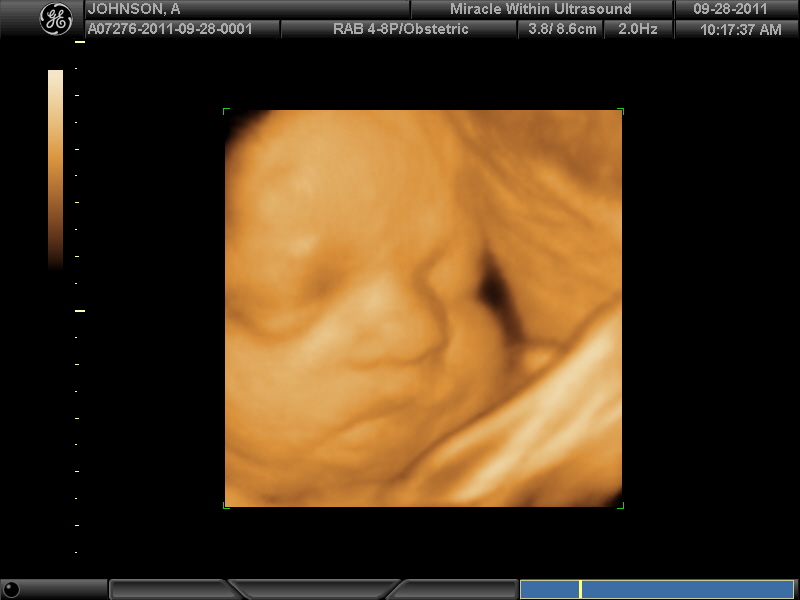

4D Ultrasound

Today I had a 4D ultrasound. Troy and I were very excited to see this little one again. We got a CD with a ton of pictures and also about a 15 minute DVD which shows the baby moving (that's what the 4D allows). There are only hand and face pictures because the technician didn't want to risk us seeing what the gender of the baby was by getting pictures of the feet. The baby cooperated wonderfully and even brought one foot up by it's face at one point. Troy and I definitely agreed that this little one looks like Luke and without question has the same button nose as Luke. We also both thought that this little one has a more round face. After having a similar ultrasound with Luke I had a strong feeling that he was a boy but with this one I feel like the features could go either way.

Notice the eyes are open in the pic below